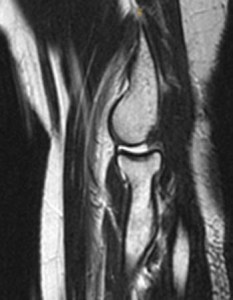

MRI scans can help to show the ligament injury: